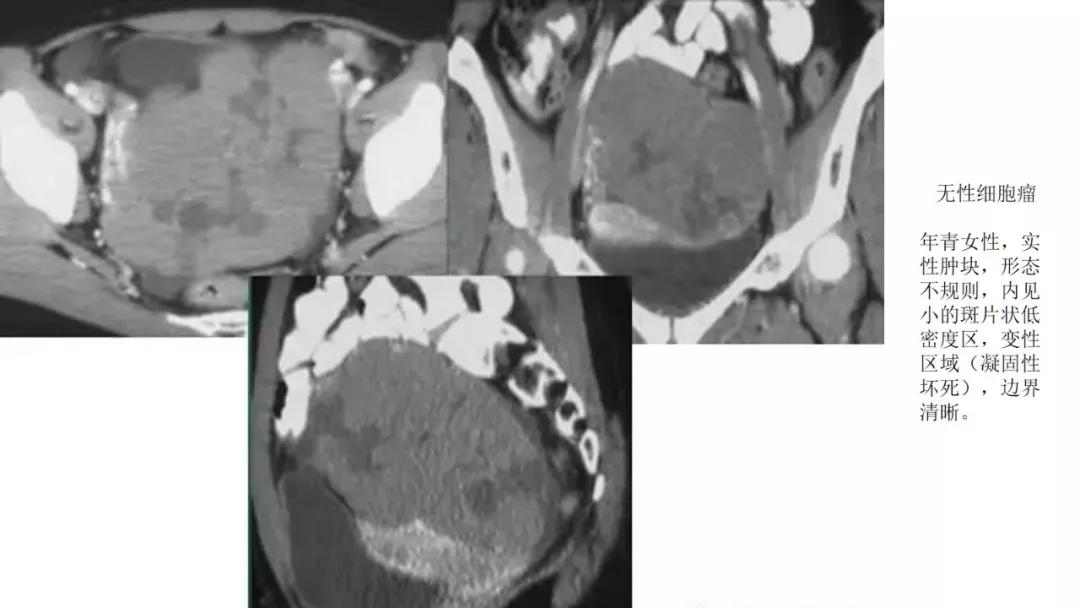

恶性者常呈实性或混杂性肿块,多数边界清楚,可伴有不规则沙粒状钙化。无性细胞瘤常为实性肿块,轻度强化,内胚窦瘤实性成分明显强化,不成熟畸胎瘤呈混杂密度。结合年龄及临床生化检查,有助于诊断。

- 纤维血管分隔呈分叶状:无性细胞瘤